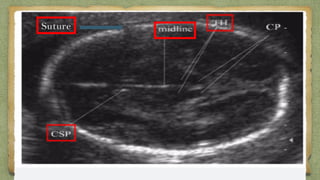

๏ฑ Correct levels

๏ฑ Measured at a focus which shows, both the THALAMITHALAMI &

the CAVUM SEPTUM PELLUCIDUMCAVUM SEPTUM PELLUCIDUM..

SutureSuture

CSPCSPThalamusThalamus